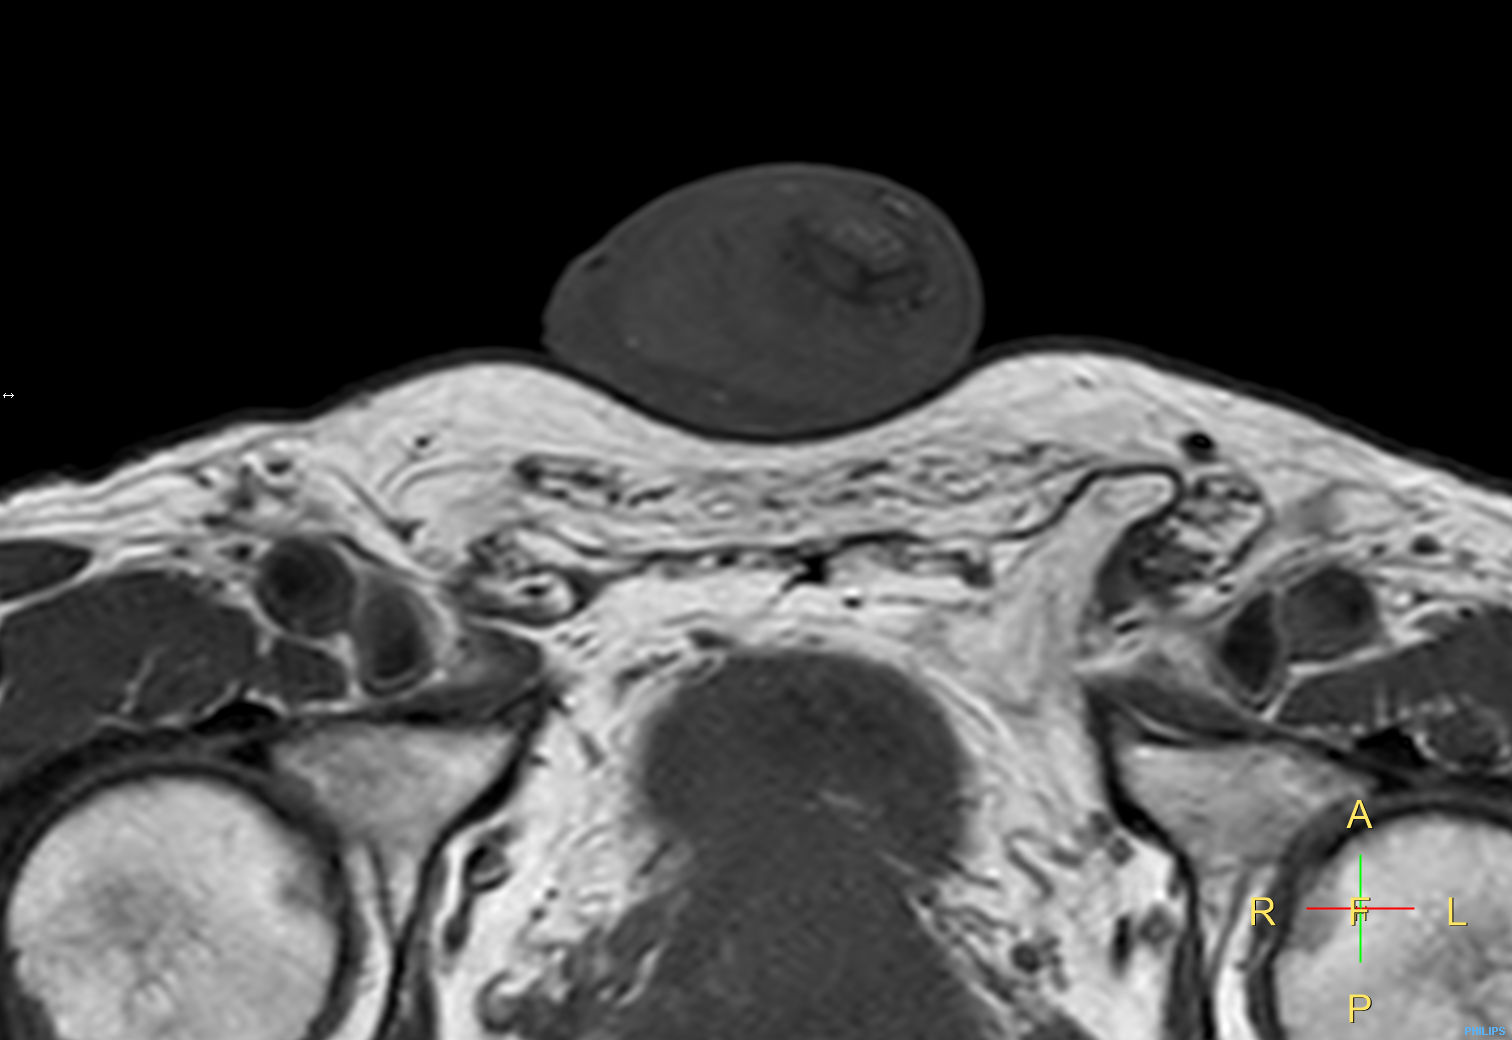

Patient with a penile carcinoma. ExamCard includes Compressed SENSE to shorten exam time, diffusion to achieve high contrast between background and lesions, and MultiVane XD for motion-free imaging in short scan time.

T2w TSE Compressed SENSE